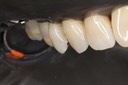

Photos of Clinical Operations

Mentors: Drs. Randy Allan, Greg Card, Peter Kearney

Clubs #44 and #50 joint meeting